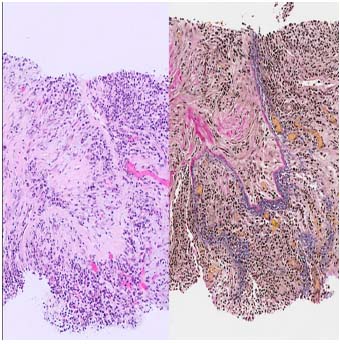

| 花むしろ様線維症(Storiform Fibrosis) | リンパ形質細胞性炎症が散在する紡錘体細胞とコラーゲン束の花むしろ様配置。このパターンでは、線維化組織は、側転のスポークに似た、炎症病巣の周囲に放射状に広がる渦巻き状または渦巻き状に配置されます。この独特の線維構造は、この疾患の特徴として広く見なされており、その組織学的認識に大きく貢献しています。 (HE染色、×100) | ![]() |

| 閉塞性静脈炎 | 中小規模の静脈は密なリンパ形質細胞性炎症によって浸潤して狭窄し、場合によっては内腔の完全な閉塞につながります(左:HE染色、x100)。EVG染色(右、×100))は血管壁の破壊を示し、閉塞性静脈炎を確認します(右)。この所見はIgG4関連疾患に特徴的ですが、常に存在するとは限りません。 | ![]() |